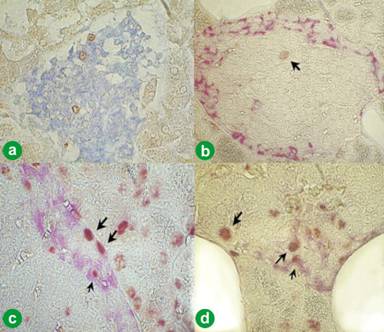

The number of individual islet, glucagon (alpha), insulin (beta), somatostatin (delta) and pancreatic polypeptide (PP) cells in each group are summarized in Figure 11 and the immunohistochemical findings are shown in Figure 12. In the HF group, the number of the beta cells was significantly higher, but that of alpha- and delta-cells were lower, in the HF group than in the other 3 groups: HF+FPE, HF+FPE+chy and control group (NP: normal pancreas of hamsters fed a commercial diet). There were no significant differences in the number of PP cells among the groups. The greater number of the alpha cells in both FPE groups was readily obvious in immunohistochemical staining (Figure 12).

Figure 12. Spatial distribution of islet cells. a. High fat (HF) diet group. Double staining showed that 19% of the cells react with anti-glucagon (blue) and 7% with anti-somatostatin antibody (red) (avidin-biotin-peroxidase complex (ABC), x50). b. In the fungal pancreatic enzyme (HF+FPE)-treated group, 25% of the cells react with anti-glucagon (blue) and 10% with anti-somatostatin antibody (brown). Note that the number of both glucagon and somatostatin cells is higher in FPE-treated hamster (b.) compared to the islets in the HF group (a.) (ABC, x50). |

Figure 13. Labeling index of islet cells. a. High fat (HF) diet group (blue: insulin; brown: BRDU). b. Fungal pancreatic enzyme (HF+FPE)-treated group (red: glucagon; brown: BRDU). c. HF+FPE-treated group (red: glucagon; brown: BRDU). Large arrows: BrdU labeled delta-cell. Small arrow: BrdU labeled alpha-cell. d. HF+FPE-treated group (red: glucagon; brown: BRDU). Large arrow: labeled delta-cell. Small arrow: labeled alpha-cell.